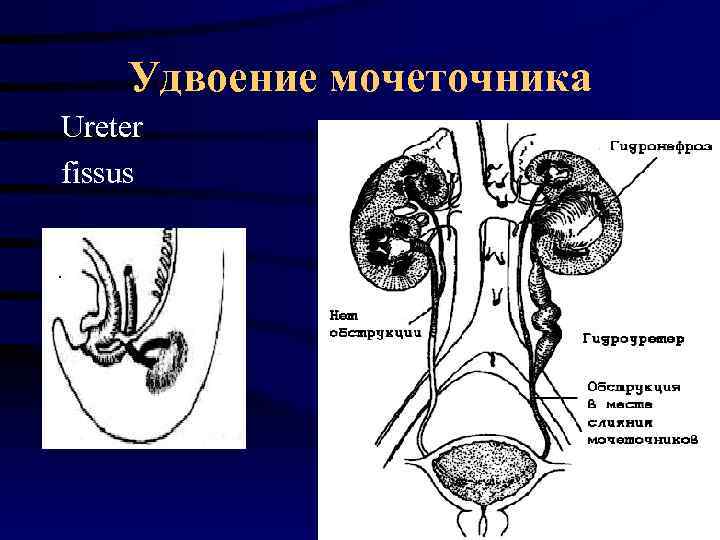

Удвоение мочеточника Ureter fissus

Удвоение мочеточника Ureter fissus